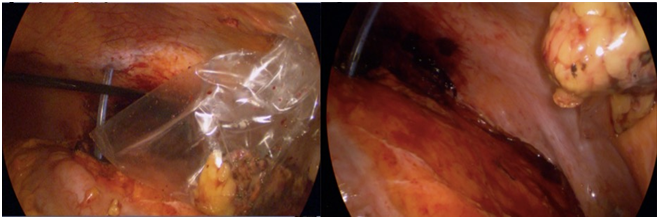

A 72 years old man was diagnosed with a small left renal mass incidentally during an ultrasonography for to an aortic abdominal aneurysm. A computer tomography (CT) scan confirm an exophytic 3cm left renal mass; therefore, an unclamped-laparoscopic partial nephrectomy was performed without difficulty. The tumor was placed inside of a plastic self-performed thermofused retrieval bag (Figure 1) and extracted trough a 12mm laparoscopic port. Finally, a drain was also placed close to the renorrhaphy. The patient was taken to the hospital room and in that moment, we realized that the bag was broken and the tumor was not inside. With the patient and family consent, a CT scan was performed showing a small mass next to the renorrhaphy (Figure 2); therefore, we decided to underwent an exploratory laparoscopy using the same port and patient position. Once laparoscopic camera was introduced, the tumor was found over the sigmoid colon slightly adhered (Figure 3) and extracted inside of a surgical glove. The hospital stay was 3 days with no perioperatory complications and the final histopathological finding was a 2cm cromophobo renal cell carcinoma with negative surgical margins.

Figure 3 Tumor over the sigmoid colon.

Partial nephrectomy is now the standard of care for small renal masses because it has the same oncological outcomes and better functional outcomes compare to radical nephrectomy. Laparoscopic partial nephrectomy is worldwide increasingly due to minimal invasive advantages especially avoiding the so painful incision as lumbotomy and showing similar results compare to conventional approach. Nevertheless, LPN need to be performed in an experience laparoscopic surgeon accompanied by technology and different devices such as clips, preferably Hem-O-lok clips (Weck Surgical Instruments, Teleflex Medical, Durham, North Carolina), hemostatic agents, vessel seal instruments and retrieval bags. Despite they are not strictly necessary; they facilitate and increase surgical outcomes. Some of them cannot be replaced; however, others could be self-performed like retrieval bags in order to decrease surgical costs, position that occurs frequently in underdeveloped countries. In this case report, retrieval bag was broken during its extraction leaving the specimen inside even when it was gently extracted. Any report has been published in the literature that allows what to do in similar circumstances. Many questions were discussed such as leave the tumor inside knowing that only 24% of these small renal masses have an aggressive histology,4 there are no literature that described natural history of leaving these tumors inside; to reexplore surgically, the so small tumor was going to be found or which surgical position is going to be opted. Fortunately, the tumor was easily located with the patient placed in the same position described for transperitoneal laparoscopic renal access.